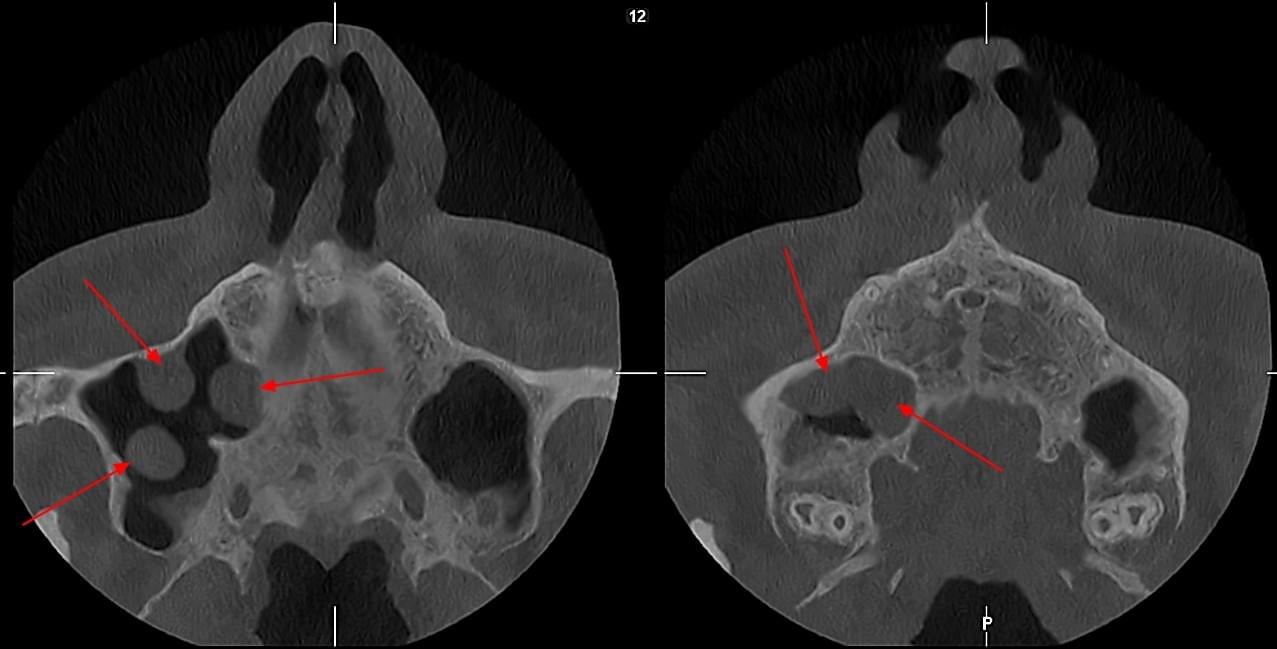

КПКТ (конусно-променева комп’ютерна томографія) — це 3D-знімок високої роздільної здатності. На відміну від звичайного рентгену, КТ показує: